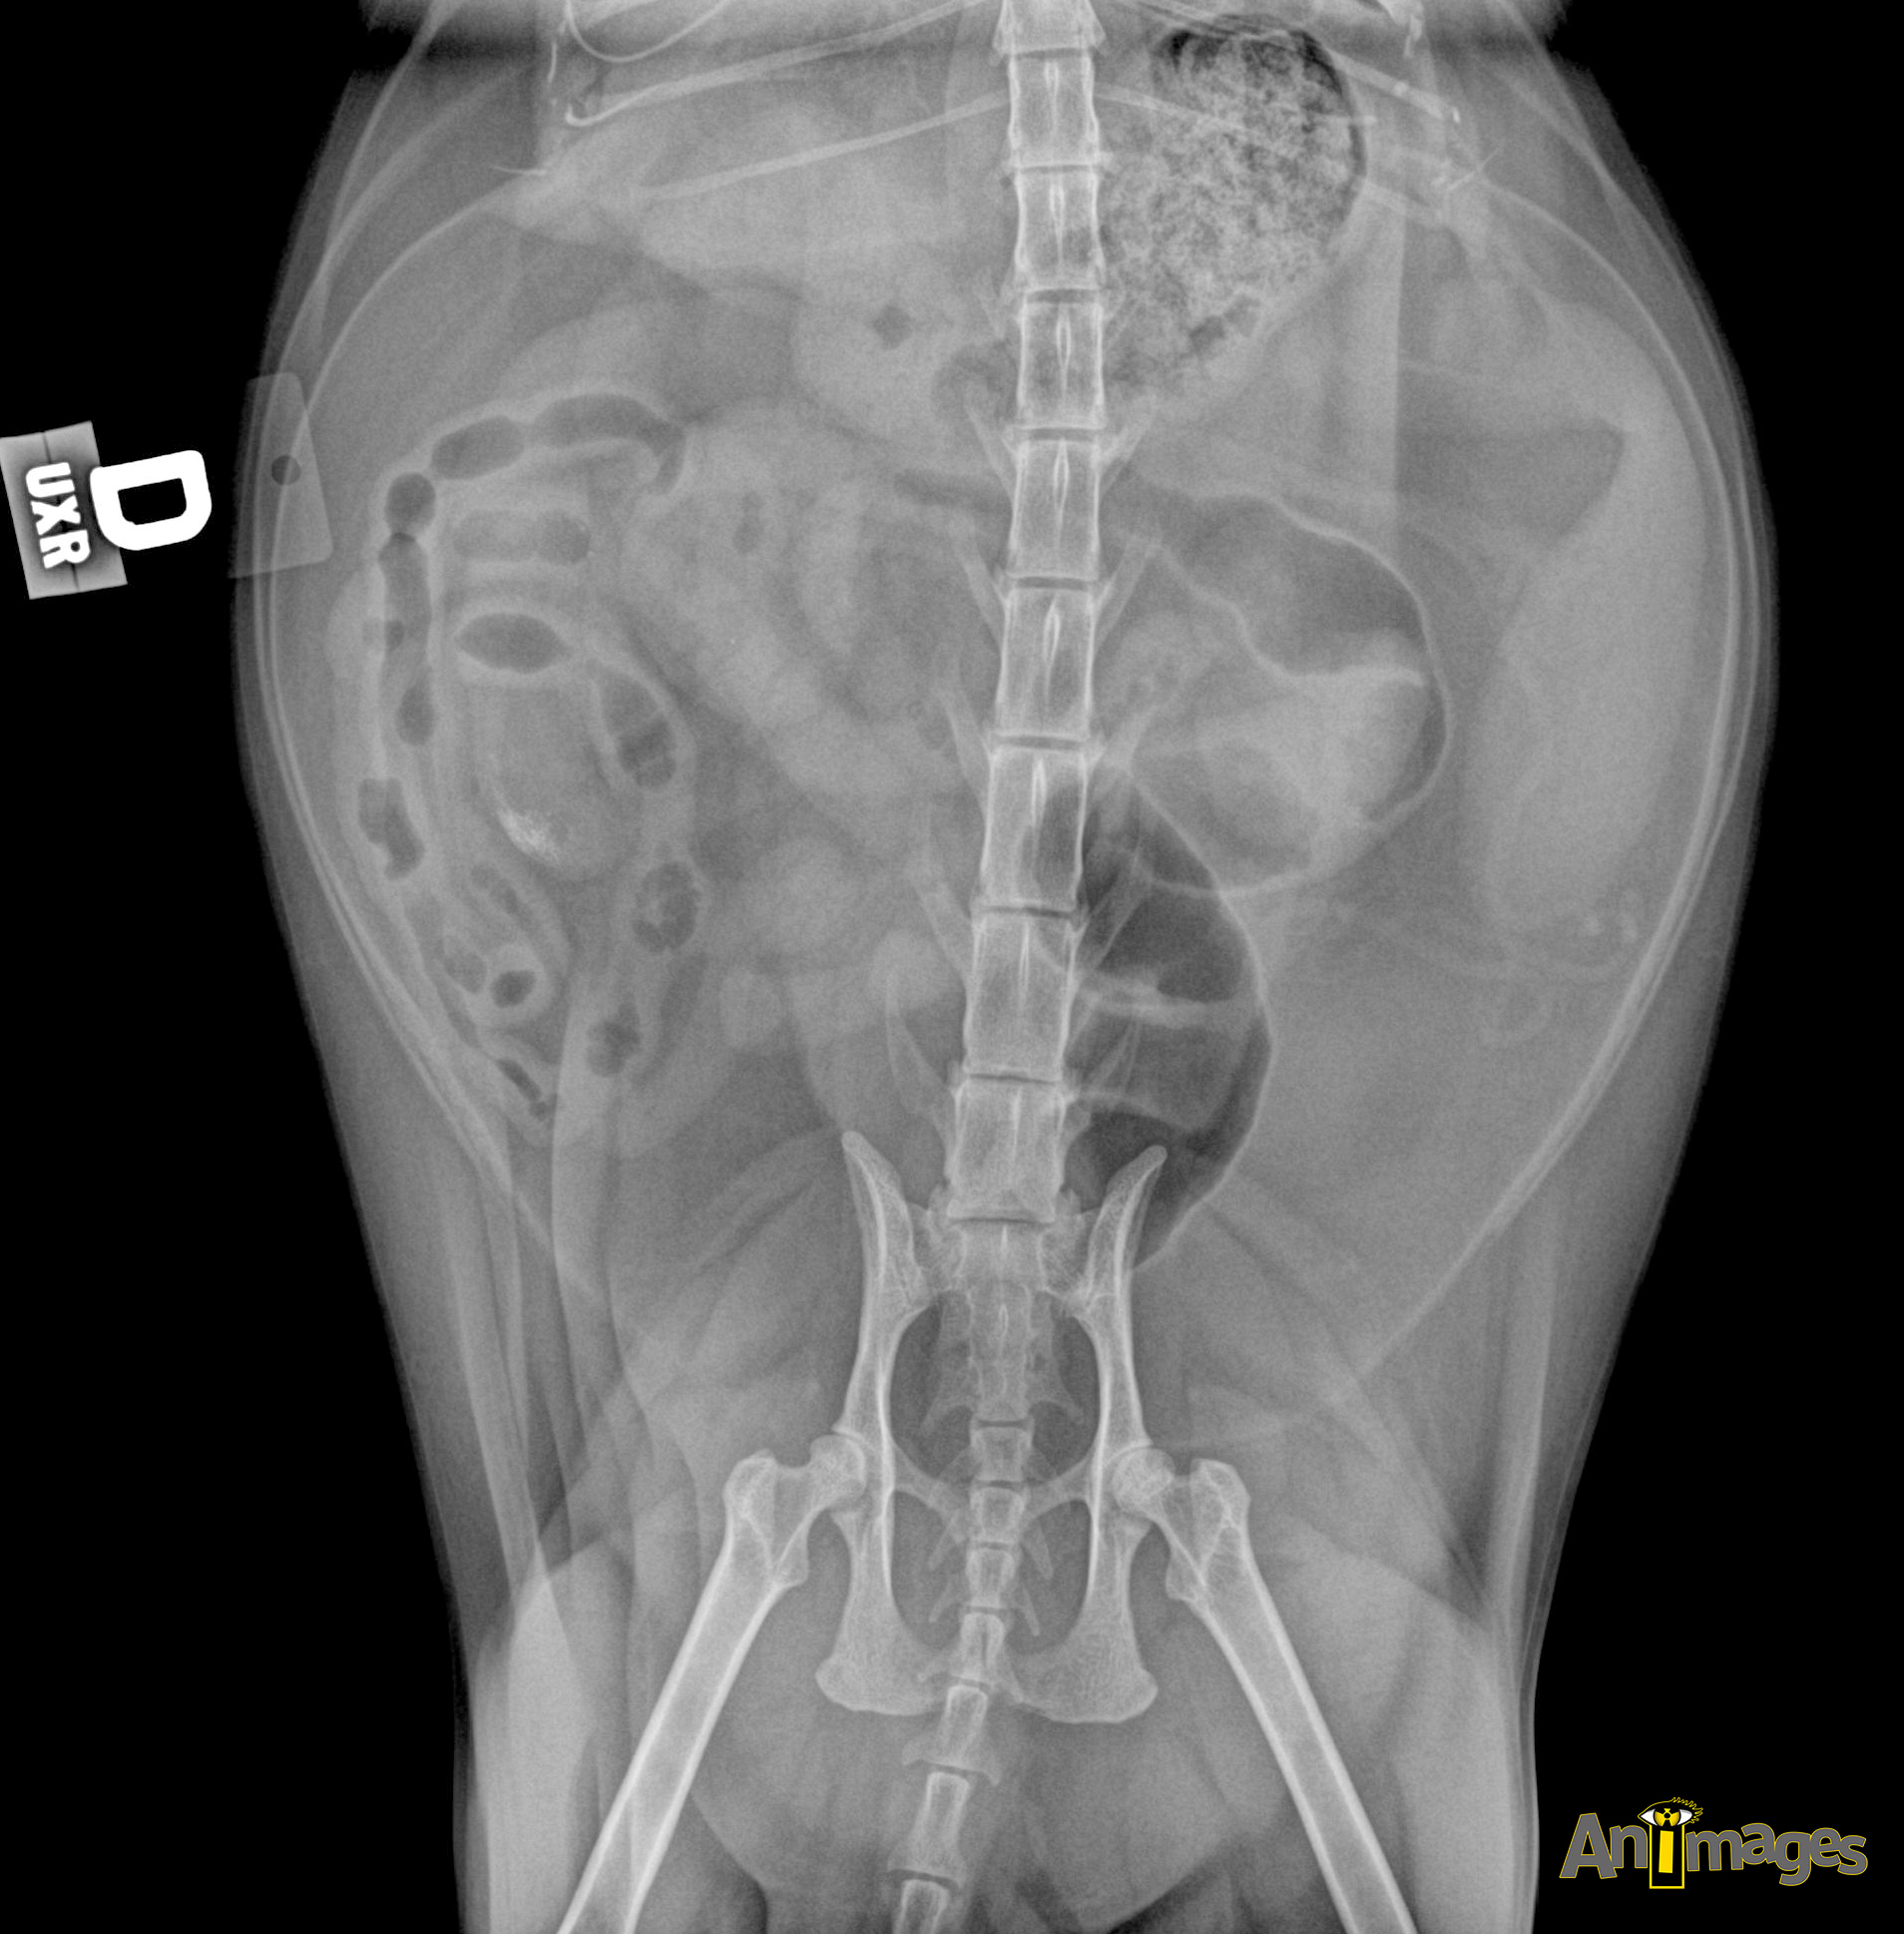

VD

- Publié 21 septembre 2017 à 1908 × 1938 dans Qu’est-ce que cette structure ?!

La rate